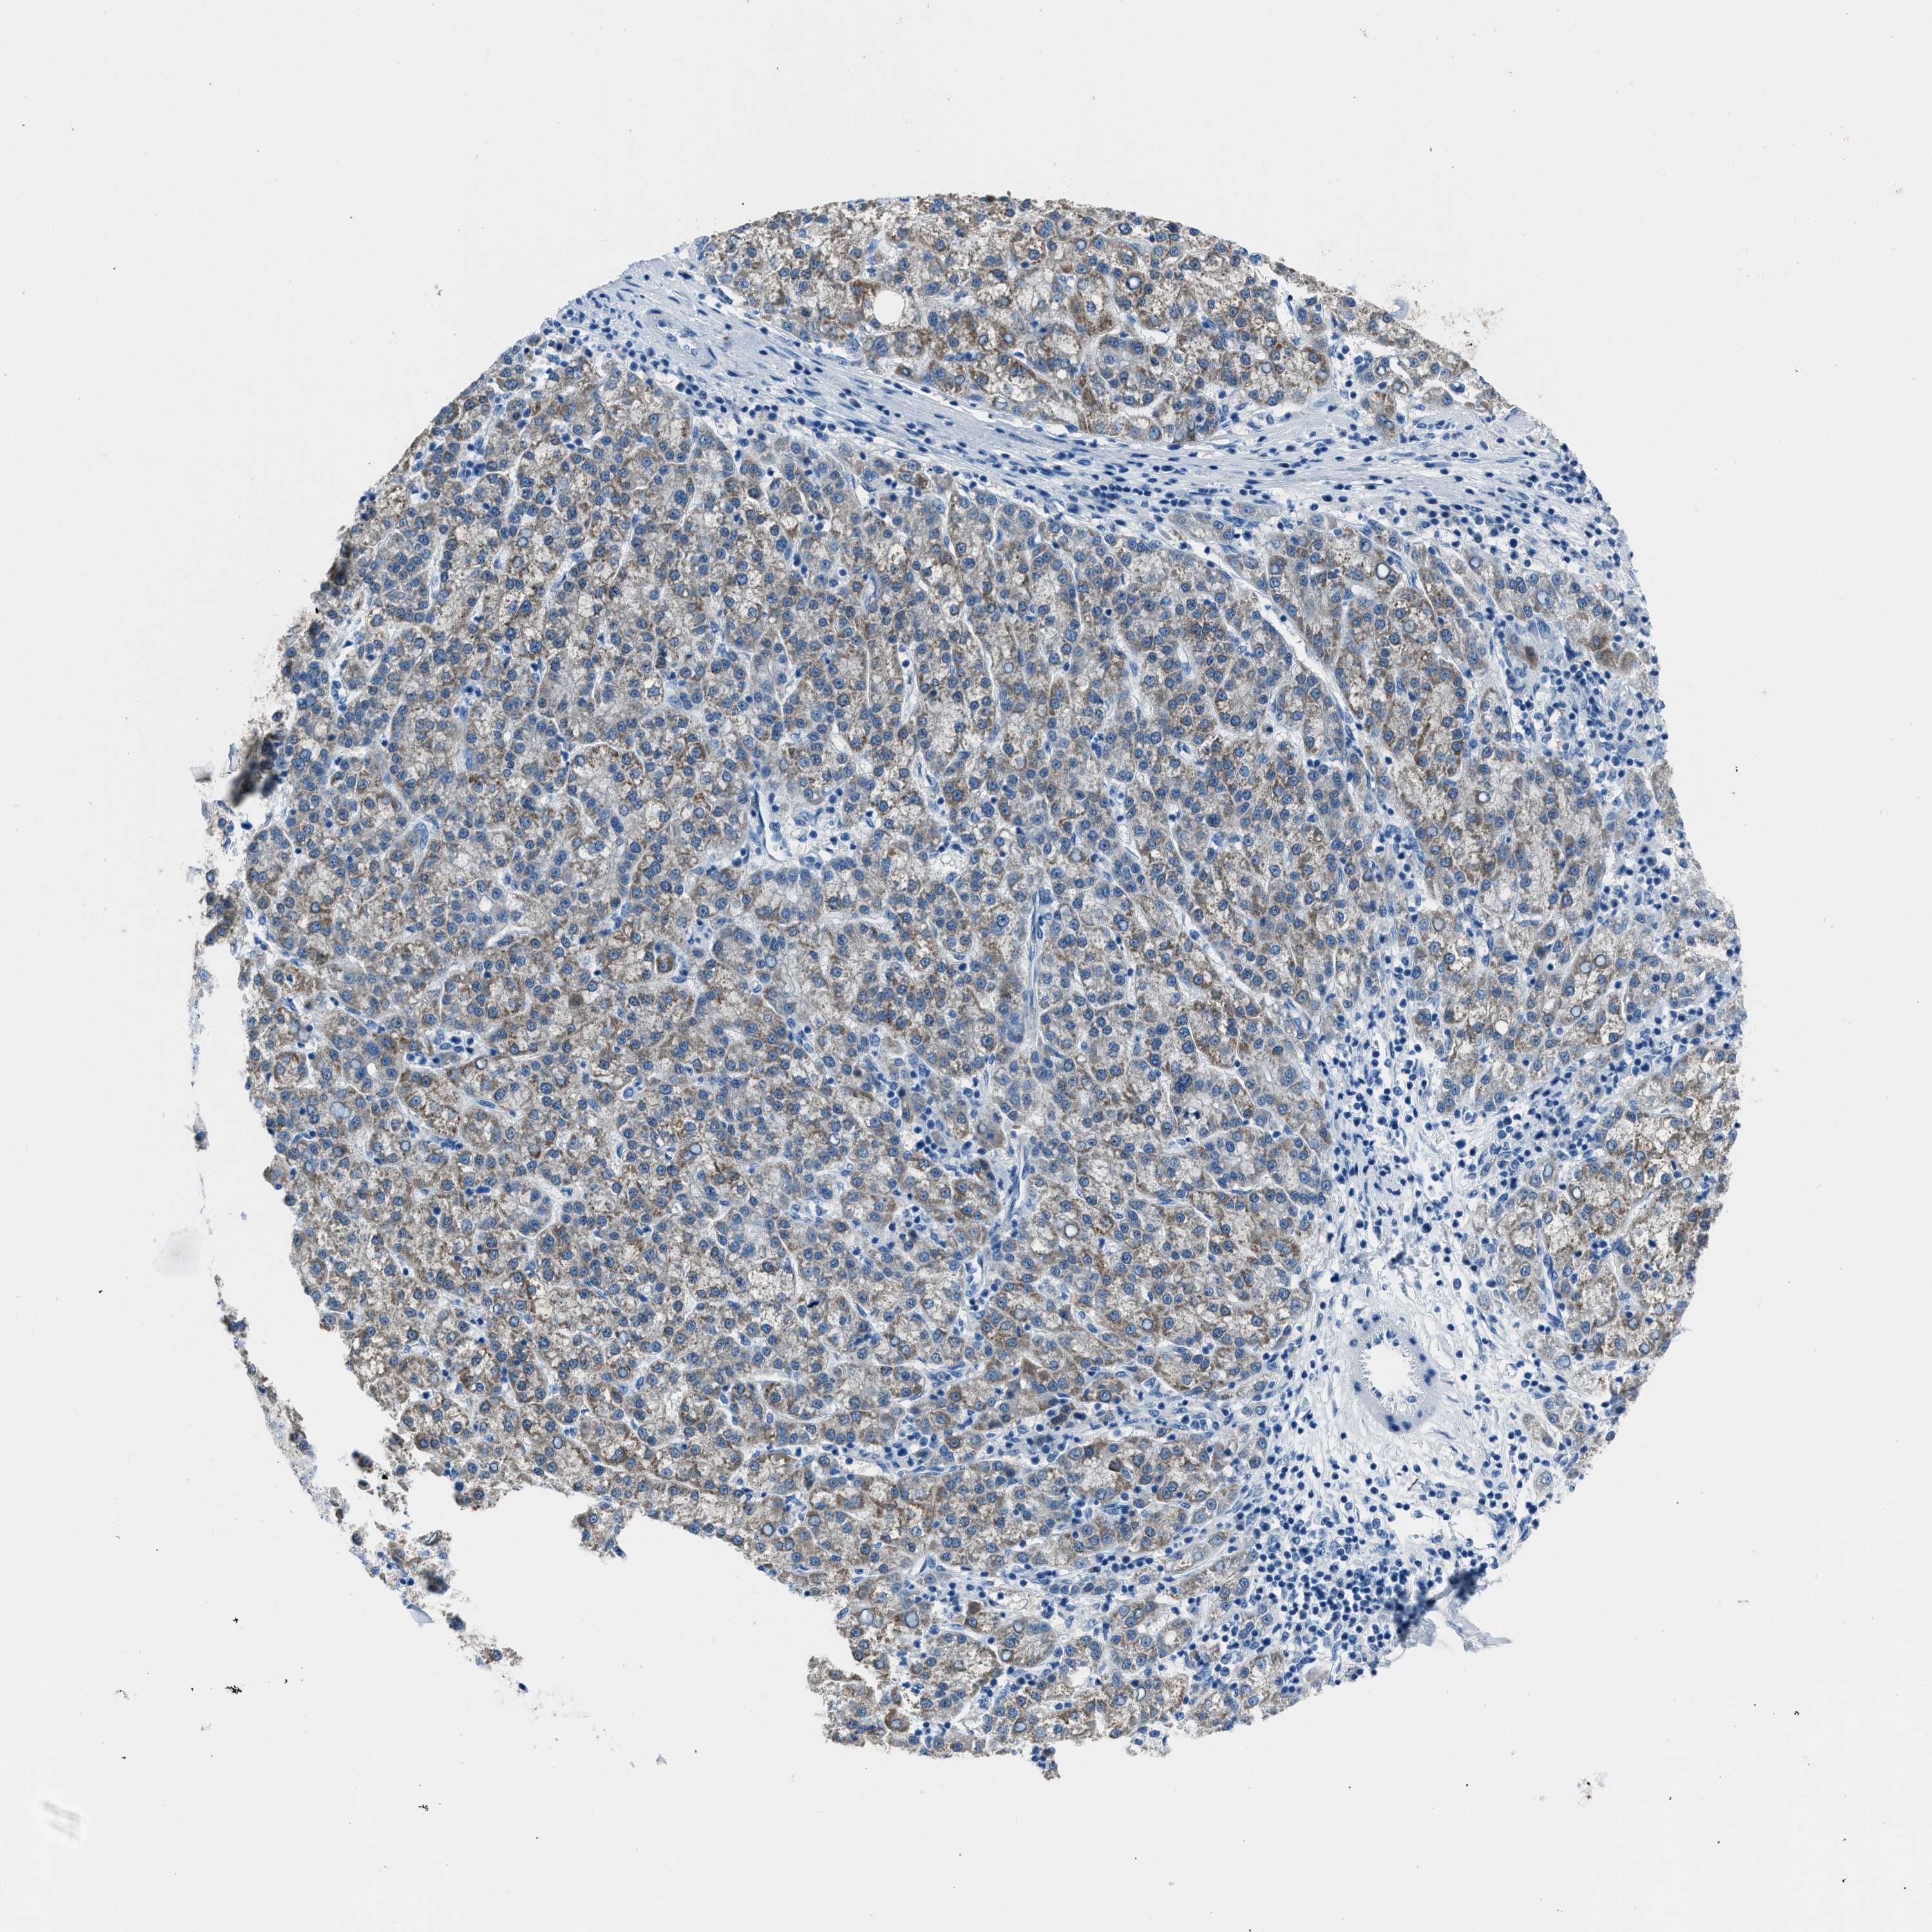

LIVER CANCER - Protein expressioni

A mouse-over function shows sample information and annotation data. Click on an image to view it in a full screen mode. Samples can be filtered based on level of antibody staining by selecting one or several of the following categories: high, medium, low and not detected. The assay and annotation is described here.

Note that samples used for immunohistochemistry by the Human Protein Atlas do not correspond to samples in the TCGA dataset.

Antibody stainingi

Antibody staining in the annotated cell types in the current human tissue is reported as not detected, low, medium, or high, based on conventional immunohistochemistry profiling in selected tissues. This score is based on the combination of the staining intensity and fraction of stained cells.

Each image is clickable and will lead to virtual microscopy that enables deeper exploration of all samples and also displays staining intensity scores, fraction scores and subcellular localization as well as patient and tissue information for each sample.

Antibody HPA019527

Antibody HPA020912

Antibody CAB001809

Staining

High

Medium

Low

Not detected

Intensity

Strong

Moderate

Weak

Negative

Quantity

>75%

75%-25%

<25%

None

Location

Nuclear

Cytoplasmic/membranous

Cytoplasmic/membranous,nuclear

Cholangiocarcinoma

Carcinoma, Hepatocellular, NOS